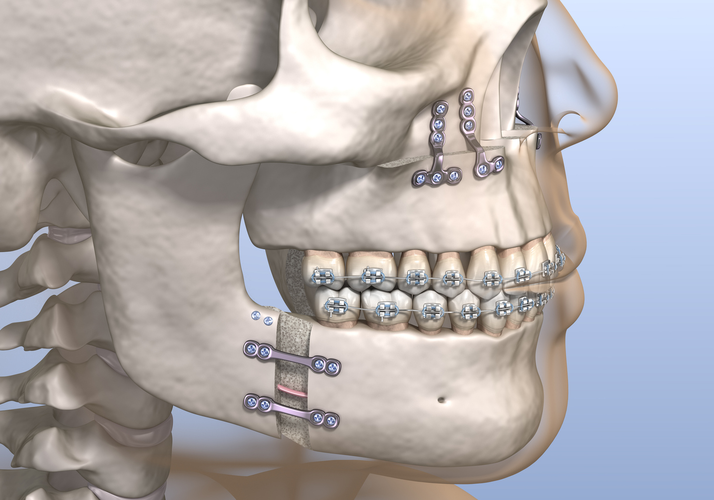

- Bimax (bimaxillary osteotomy) involves repositioning two jaws — the upper (maxilla) and lower (mandible) — to correct bite issues, facial imbalance, or airway problems.

Bimax involves repositioning both the maxilla (upper jaw) and mandible (lower jaw).

3. Custom Jaw Surgery vs Traditional Jaw Surgery

- Custom / 3D Bimax / Trimax (usually done at private clinics) : Uses virtual planning and custom titanium plates for perfect symmetry and aesthetic refinement.

- Access to better planning and materials (custom plates, 3D simulations, faster recovery).